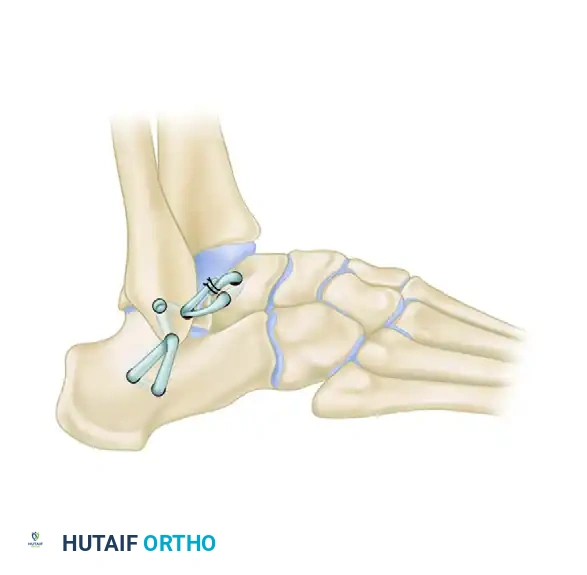

The Chrisman-Snook Modification

To address the persistent subtalar instability seen in the Watson-Jones procedure, Snook, Chrisman, and Wilson modified the Elmslie procedure. This technique uses a split half of the peroneus brevis tendon to reconstruct both the ATFL and CFL, restoring a more anatomical line of pull.

Key Modifications (1985 Update):

1. Calcaneal Tunnel: A direct tunnel is drilled in the calcaneus, which is biomechanically stronger and technically easier to create than the original "trapdoor" technique.

2. Graft Fixation: The end of the graft is sutured in front of the lateral malleolus rather than at the base of the fifth metatarsal, providing a significantly stronger repair.

3. Positioning: The foot and ankle are held in mild rather than forced eversion while the graft is tensioned and sutured.

Biomechanical cadaveric studies confirm that the Chrisman-Snook reconstruction provides superior stability to the ankle joint complex compared to the Evans and Watson-Jones procedures, though it does result in a slight, permanent reduction in physiologic inversion motion.

The Sammarco and DiRaimondo Modification

For high-demand athletes, patients with long-standing combined ankle and subtalar instability, or those undergoing revision for a failed primary reconstruction, Sammarco and DiRaimondo developed a robust modification of the Elmslie technique.

Surgical Steps:

1. Graft Harvest: A split peroneus brevis tendon graft is harvested proximally from the musculotendinous junction and pulled beneath the skin into the distal incision.

2. Osseous Tunnels: Drill holes are placed in the talar neck, the lateral malleolus, and the calcaneus. These tunnels are connected beneath 1.0- to 1.5-cm bony bridges to prevent cortical blowout.

3. Graft Routing and Reinforcement: The split tendon graft is passed through the bony tunnels,